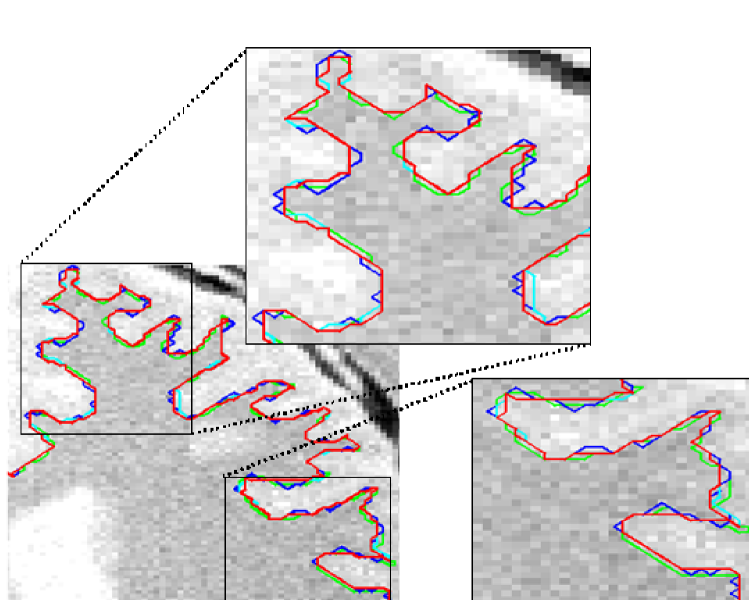

We also tested our method on clinical MR images of the corpus callosum (CC), which exhibits the known problem of a weak boundary where the CC meets the fornix (Fig. 3). Note how the contour obtained using globally optimal weights exhibits an optimal, yet undesirable, bimodal behavior (either blue or red in Fig. 3) completely favoring only one of the terms at a time. In comparison, our method automatically boosts up the regularization (stronger red in Fig. 3) at the CC-fornix boundary producing a better delineation. The segmentation results of all three methods for the same image are shown in Fig. 4.

We also tested our method on MR data from BrainWeb [21]. Fig. 5 shows the segmentation of the cortical surface in a proton density (PD) image with a noise level of 5%. This example is a difficult scenario due to the high level of noise and low resolution of the image. Our proposed method provided a smoother contour while conforming to the cortical boundary when compared to the other methods (although the difference was not too large).